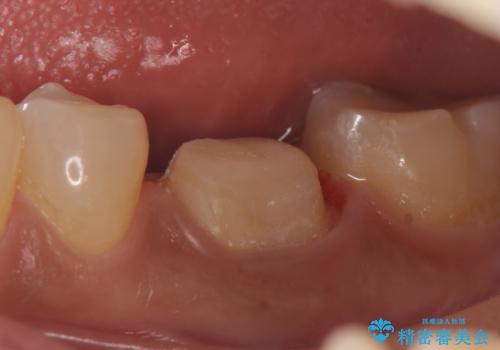

- 他院にて左下6の治療をしていたが、症状が引かないため当院にいらっしゃった方の症例です。

検査の結果左下6は神経が死んでいたため、根管治療を行いました。